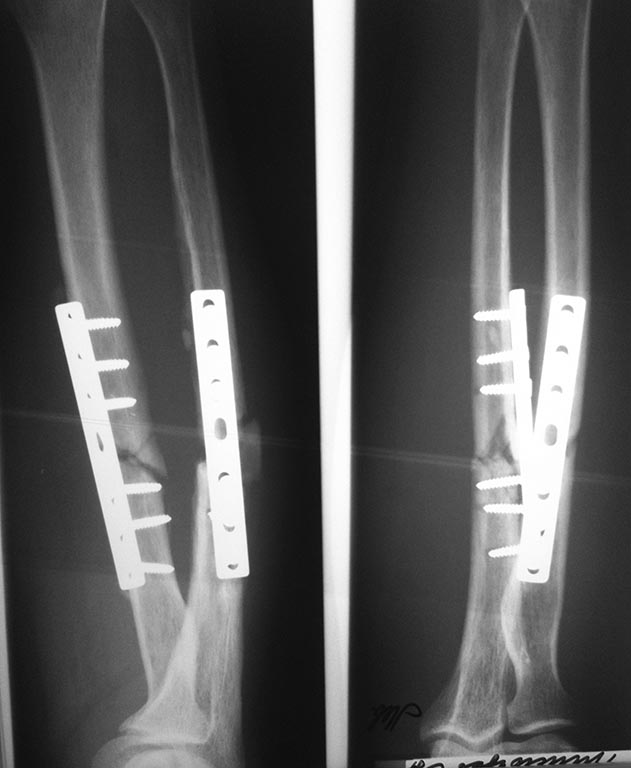

тяжелого предмета- ствола дерева (снимок 1). 03.02.15 оперирован-

остеосинтез обеих костей левого предплечья пластинами (снимков

непосредственно после операции не нашел) . Послеоперационный период

гладкий, выписан на амбулаторное долечивание. Проводилась иммобилизация

гипсовым лонгетом и косыночной повязкой в течение полутора месяцев, ЛФК

для кисти, затем начат курс ЛФК для локтевого сустава. Был на

контрольном осмотре в марте 2015,особых жалоб не предъявлял, проводилось

ФТЛ, ЛФК по месту жительства (снимок 2).